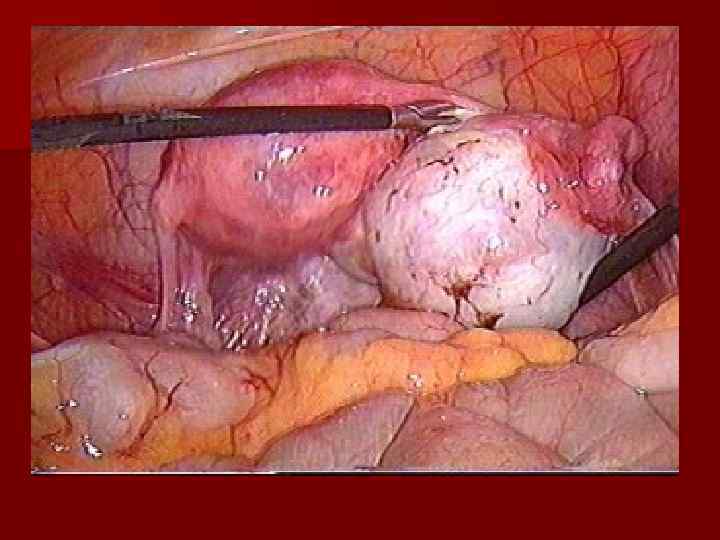

ТРУБНО-ПЕРИТОНЕАЛЬНОЕ БЕСПЛОДИЕ n ФУНКЦИОНАЛЬНАЯ ПАТОЛОГИЯ МАТОЧНЫХ ТРУБ n ОРГАНИЧЕСКАЯ ПАТОЛОГИЯ МАТОЧНЫХ ТРУБ

ТРУБНО-ПЕРИТОНЕАЛЬНОЕ БЕСПЛОДИЕ

ЛЕЧЕНИЕ n КОРРЕКЦИЯ ЭНДОКРИННЫХ НАРУШЕНИЙ, СТИМУЛЯЦИЯ ОВУЛЯЦИИ n МЛС (САЛЬПИНГООВАРИОЛИЗИС, САЛЬПИНГОСТОМИЯ, КОАГУЛЯЦИЯ ОЧАГОВ ЭНДОМЕТРИОЗА И Т. Д. ) n ВРТ